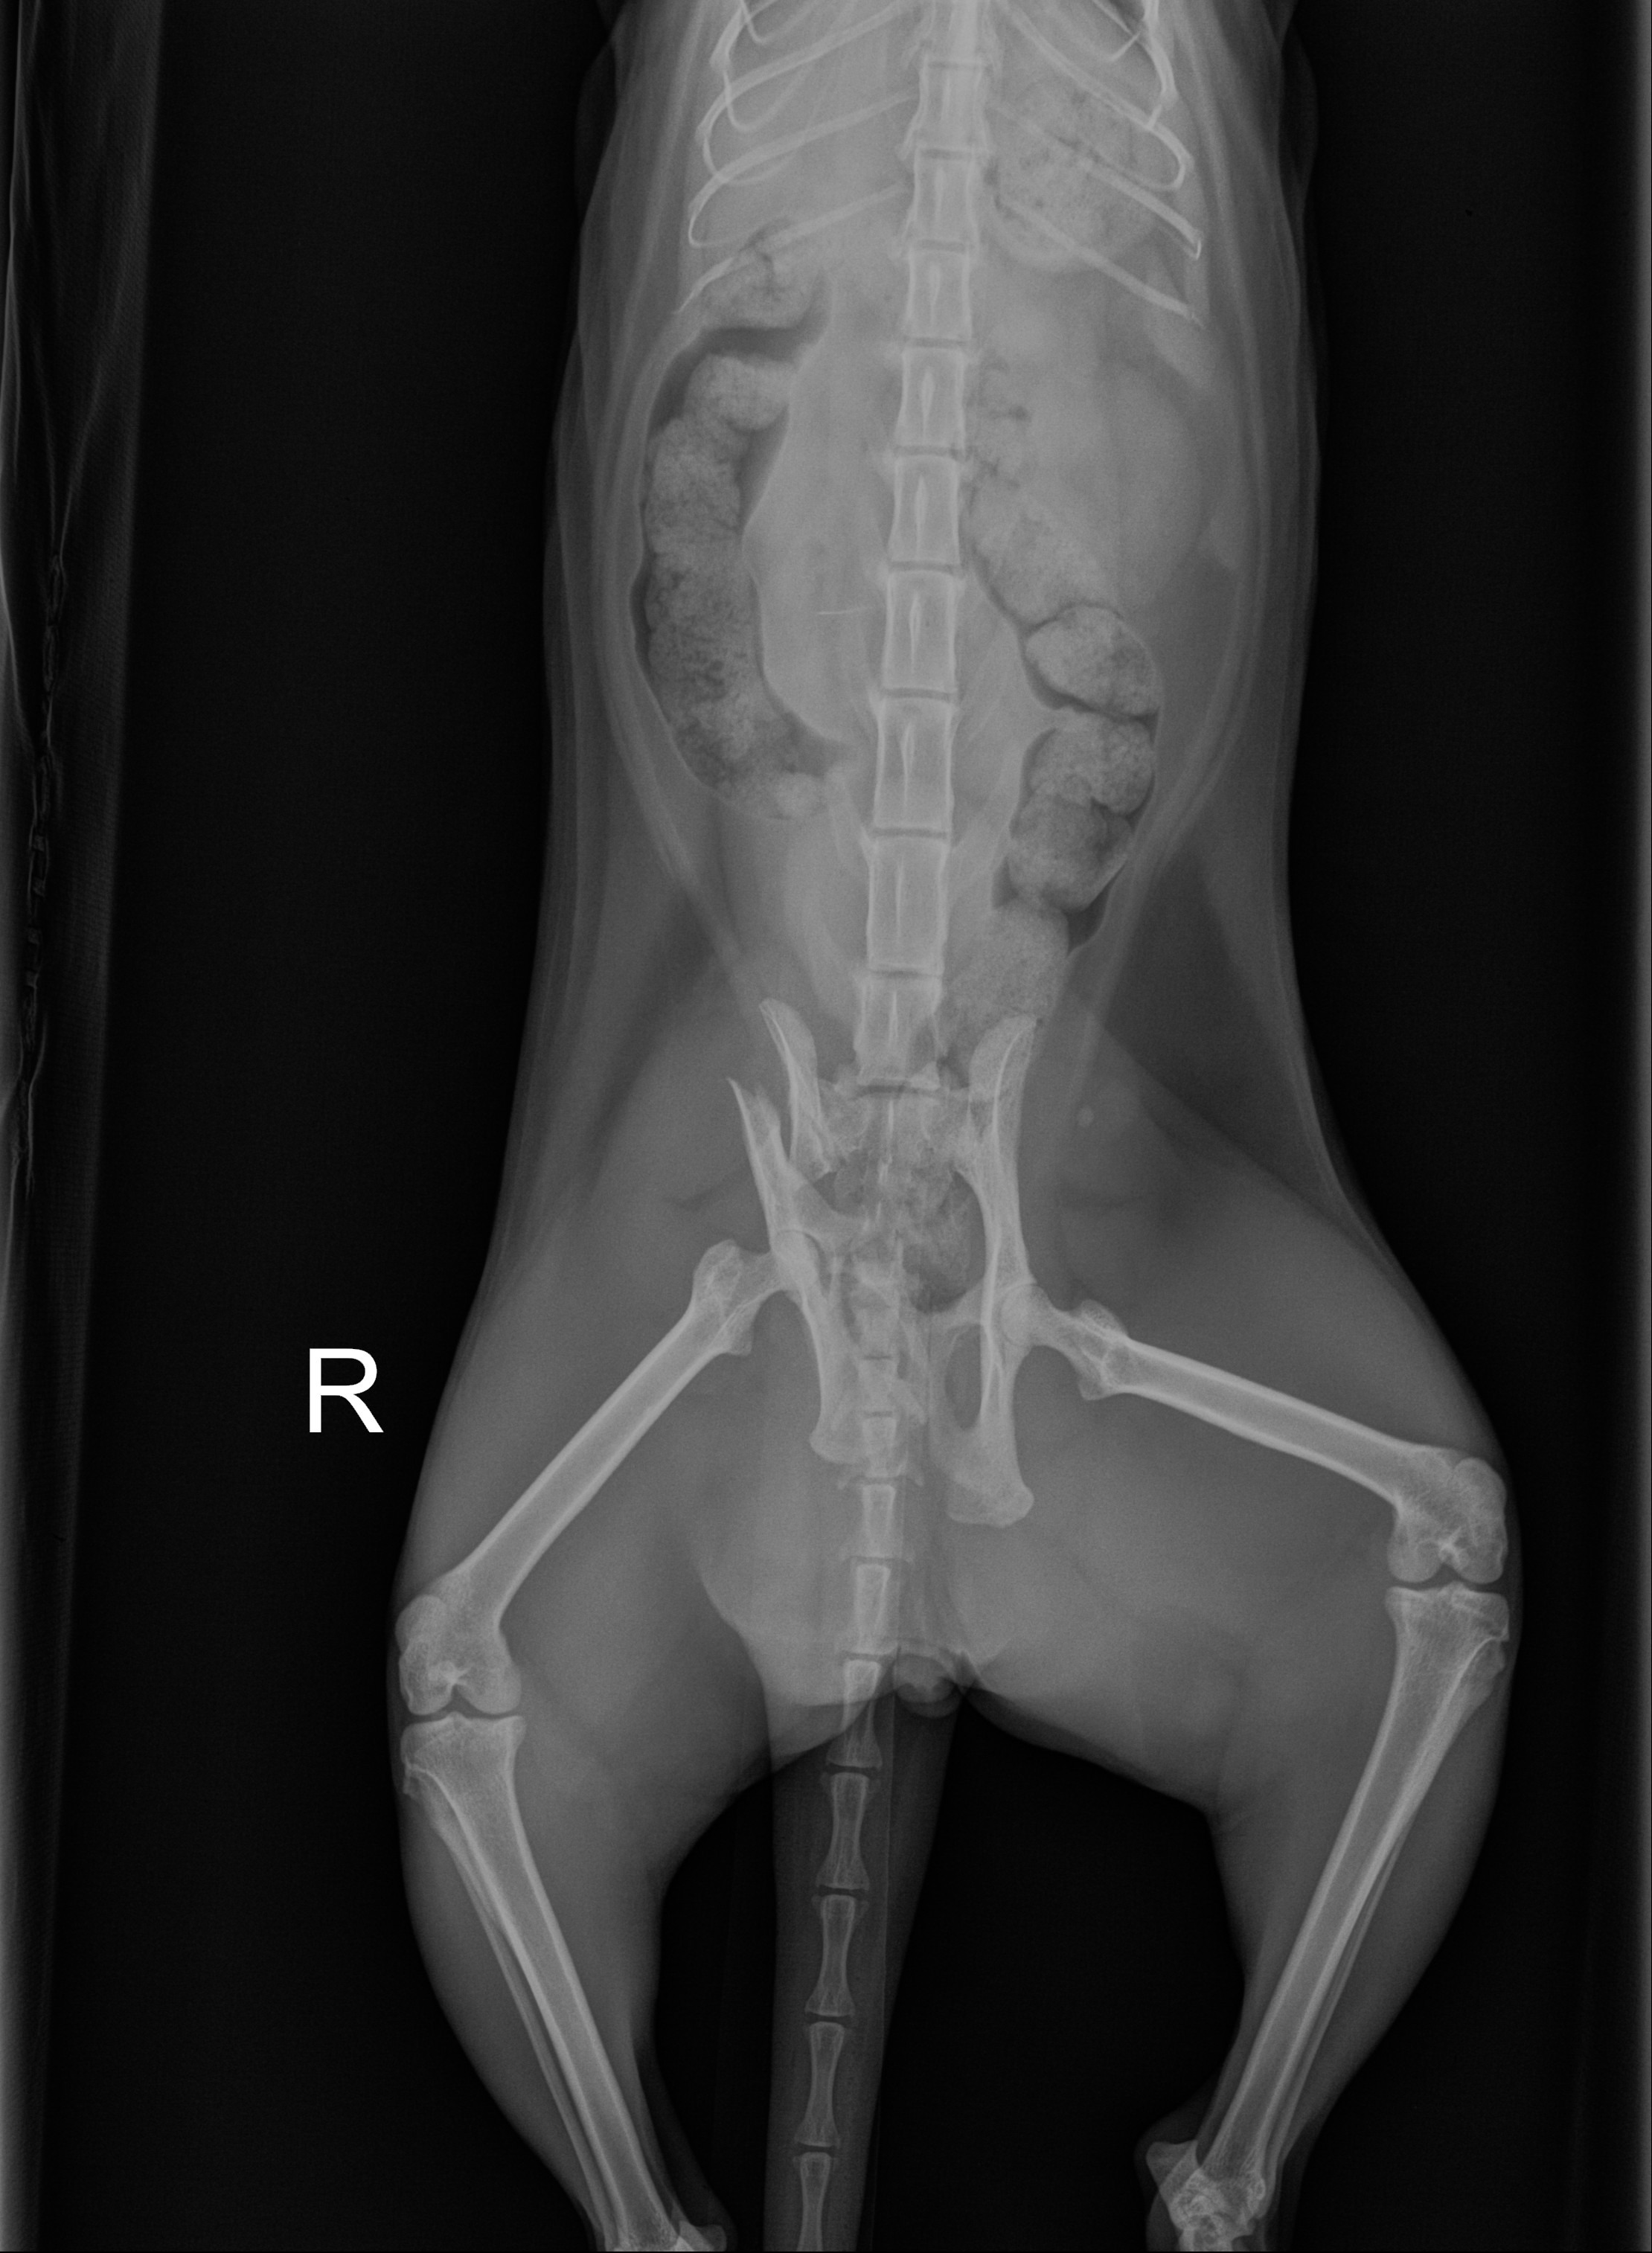

X-rays revealed that his pelvis is displaced in a way that requires surgery from a specialized orthopedic surgeon. Without this procedure, Cobalt won’t be able to heal properly or regain his quality of life. The surgery involves placing a plate to stabilize his bones, giving him the chance to walk, run, and cuddle again like the affectionate cat he is.